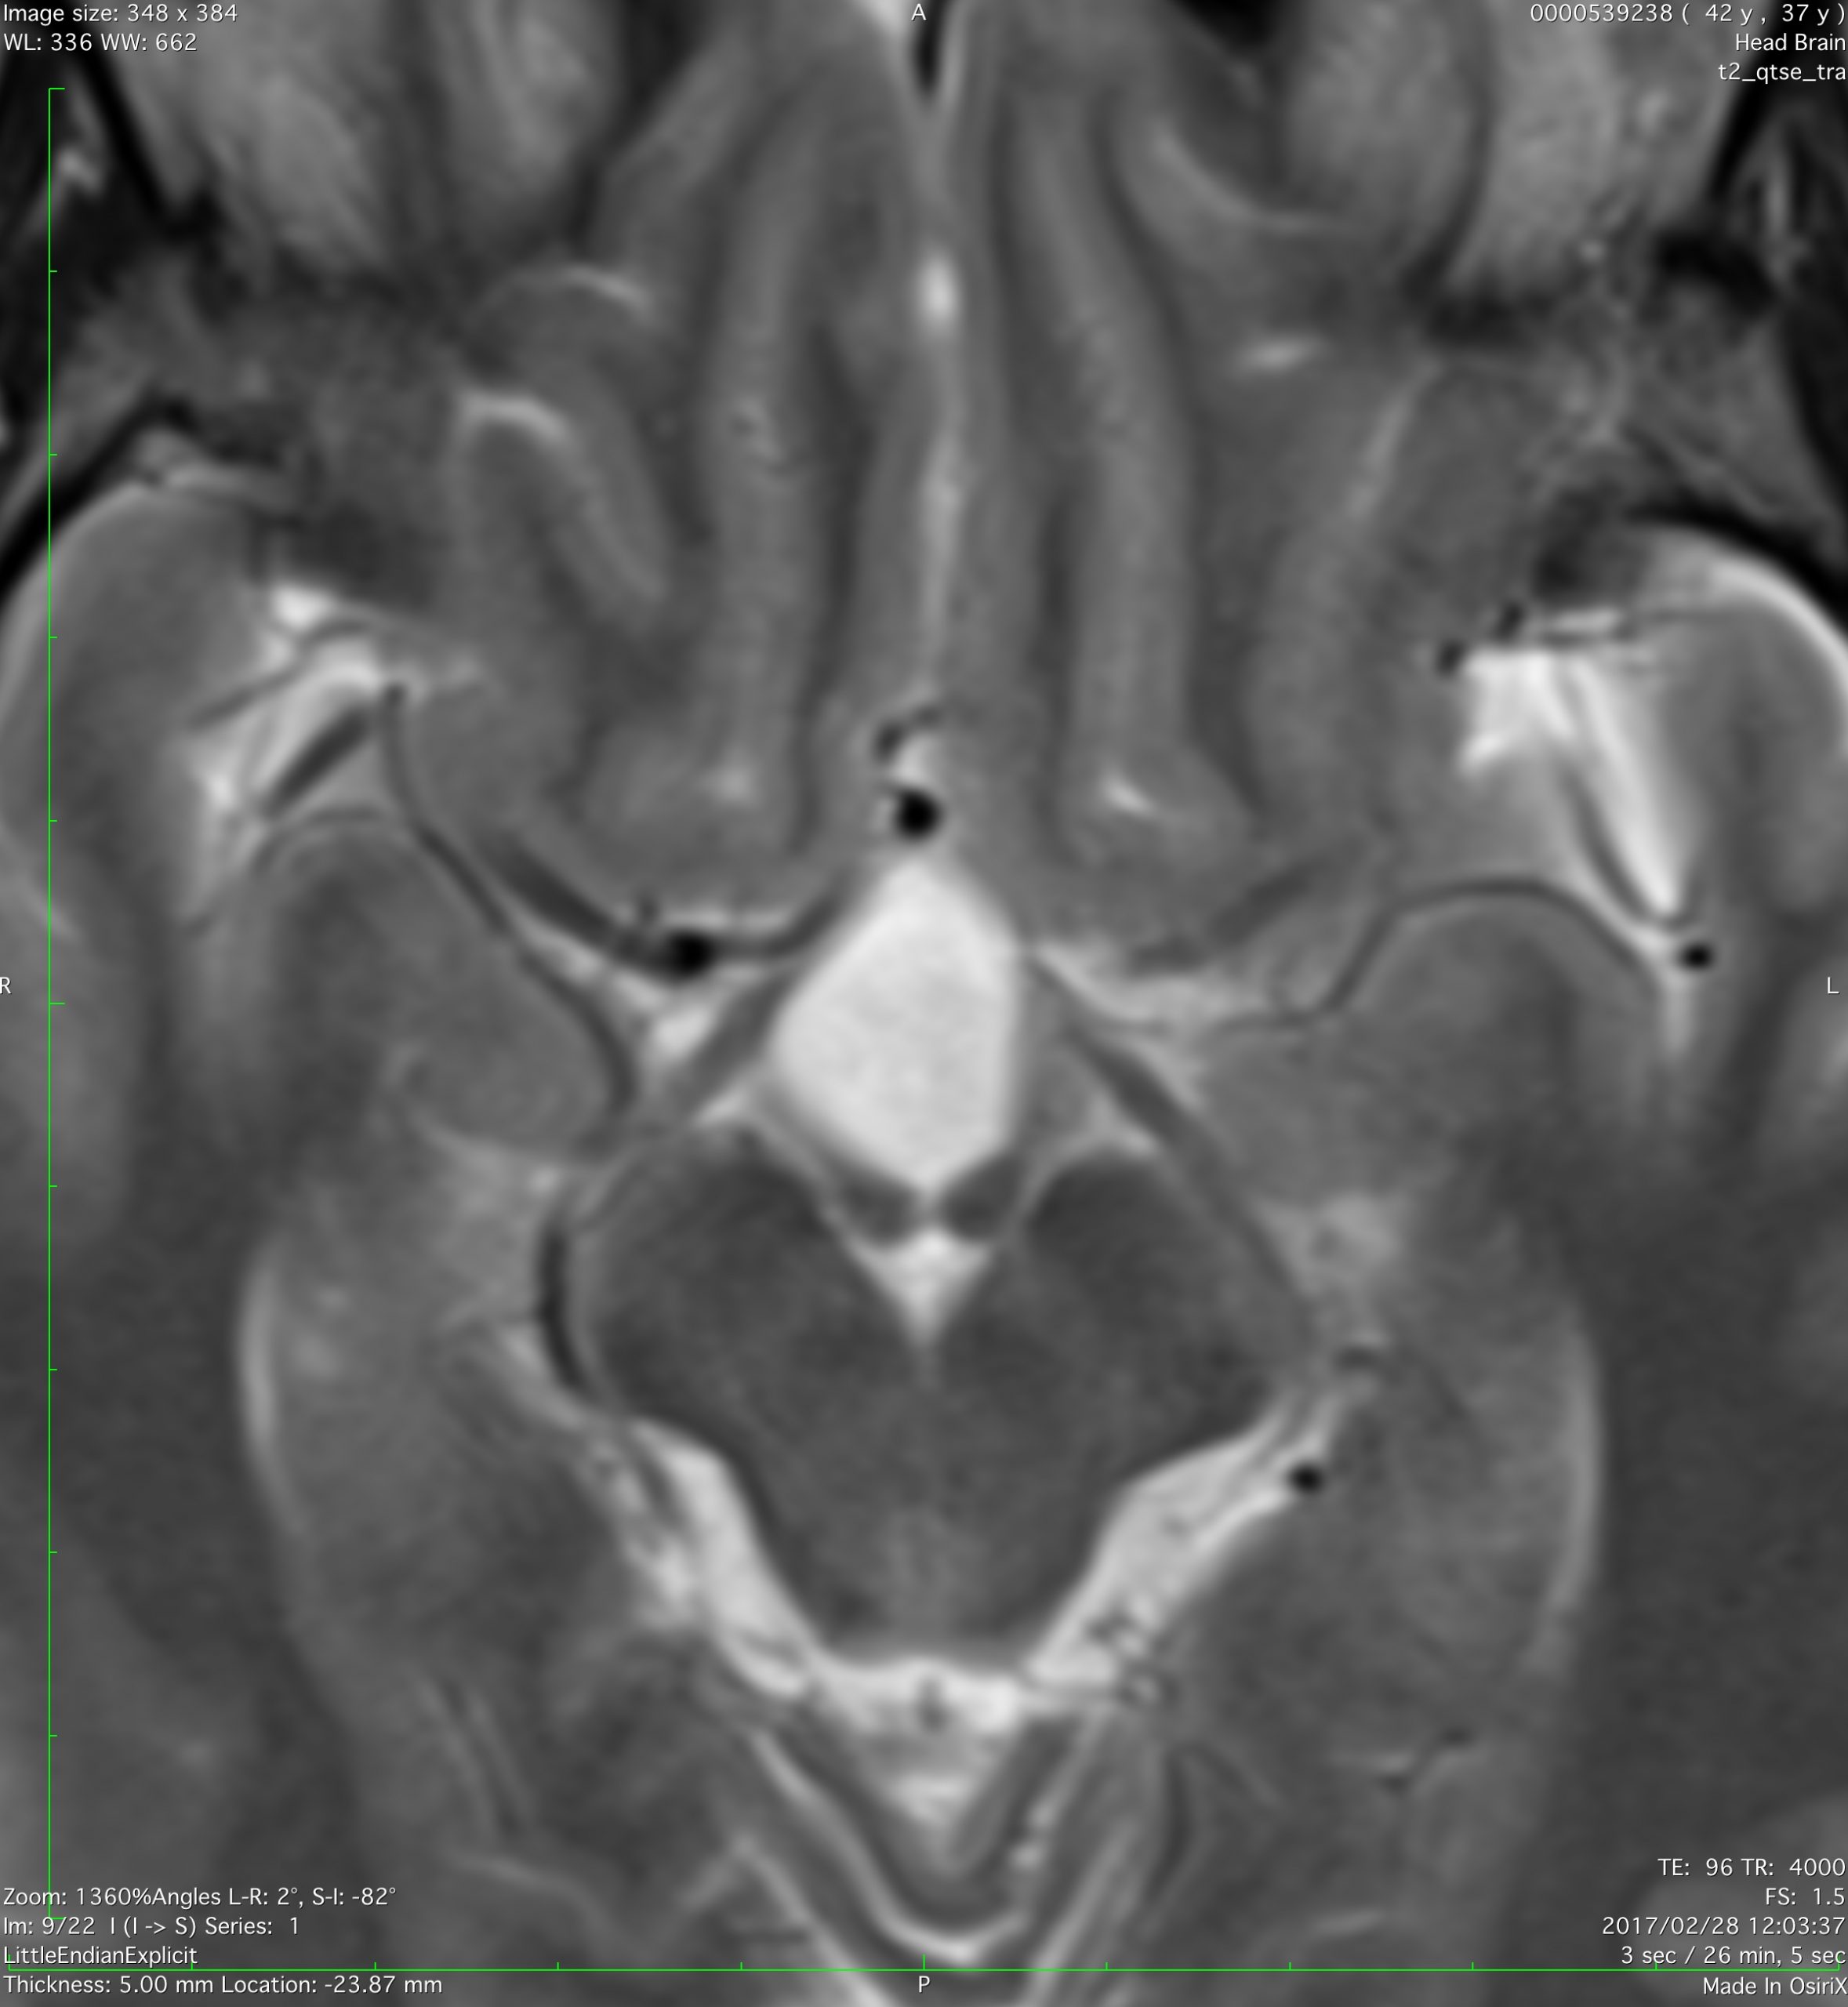

全く何もしなくても良い成人の毛様細胞性星細胞腫

20代女性に偶然発見された視床下部(第3脳室)腫瘍です,T1低信号,T2で高信号,右側のガドリニウム造影では全く増強されません。毛様細胞性星細胞腫と診断できます。眼科での視野検査で視野欠損はありませんでした。生検術もなにもせず経過をみました。

左が初診時,右が5年後のMRI画像です。腫瘍の大きさは全く同じです。このような腫瘍はしばしば経験します。慌てて生検術や開頭手術など計画しないで,画像診断をしっかりすることが大切です。